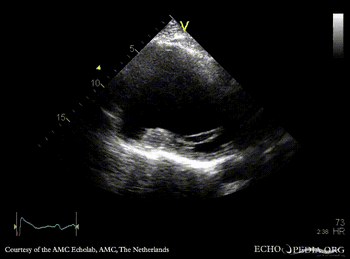

A4CH: large apical aneurysm of left ventricle, spontaneous echocontrast